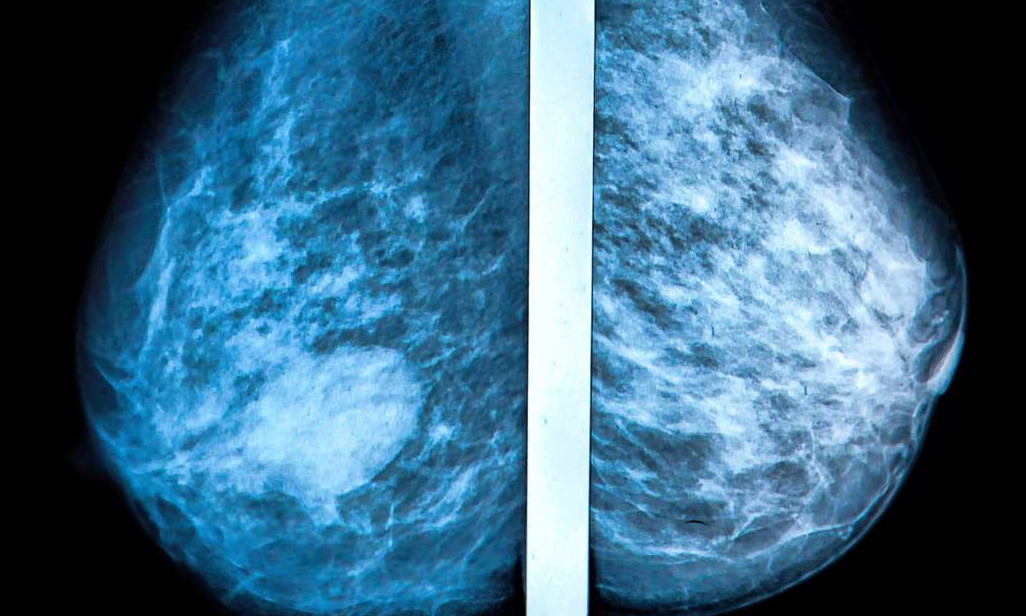

Что такое маммография: важность, процесс и результаты